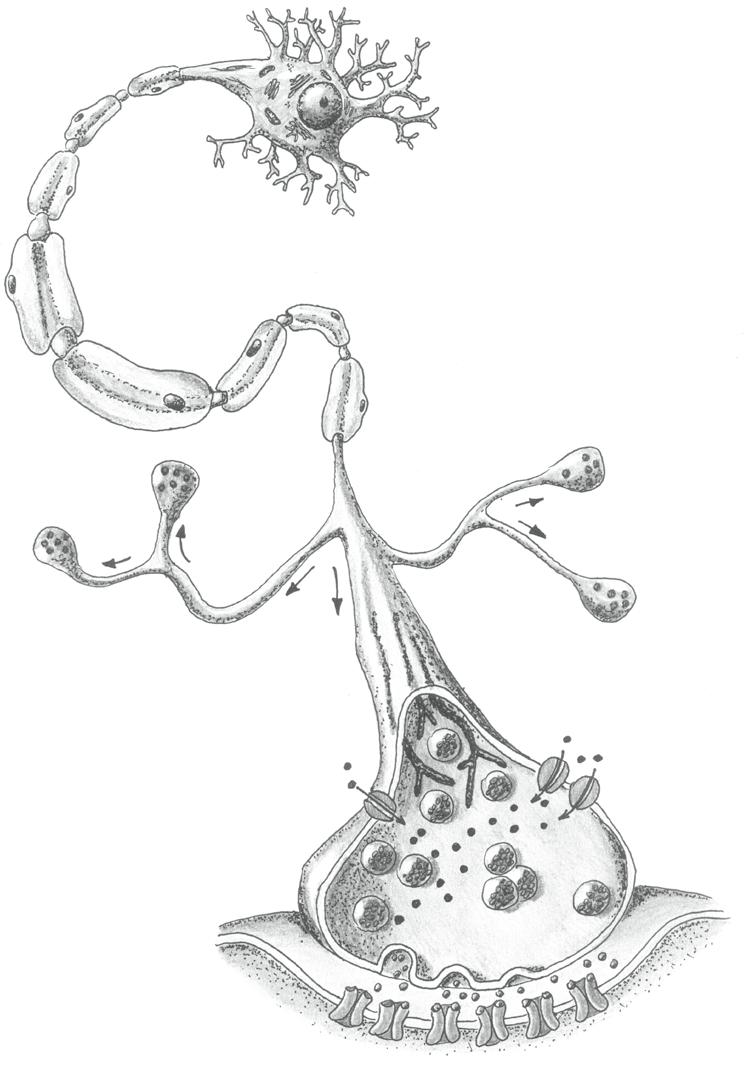

Jednotlivé neurony se liší tvarem a velikostí, ale každý z nich je tvořen třemi základními částmi: tělem a systémem výběžků, kterým říkáme dendrity a axony.

• Tělo (řecky soma) je ústřední částí každého neuronu. Obsahuje jádro a další výše zmíněné buněčné organely.

• Dendrity jsou vesměs bohatě větvené výběžky (jejich název je odvozen z řeckého slova dendron – strom). Informace v podobě elektrických potenciálů vedou vždy dostředivě – směrem k tělu nervové buňky. Jejich povrch může být zvětšen drobnými výčnělky – dendritickými trny

• Axon je většinou dlouhý výběžek nervové buňky. Vystupuje z axonového hrbolku na těle neuronu a větví se zpravidla až ve své koncové (terminální) části. Na rozdíl od dendritů vede informaci zásadně odstředivě – tedy od těla nervové buňky.

axon

axoplazma axolema

iniciální segment (axonový hrbolek)

kolaterální axon

cytoplazma

jádro myelinové vrstvy

mitochondrie

Schwannova buňka

dendrity

jádro

dendritické trny

Obr. 2.2 Nervová buňka

Ranvierův zářez

akč ní h o p o uláicnet

terminální větvení axonu

synaptický kno ík (presynaptický útvar)

pyramidová buňka

Purkyňova buňka

hvězdicová buňka

tělo neuronu

granulární (zrnité) buňky

axon axon

dendrity dendrity dendrity

koncová větvení axonu

bipolární buňka

Obr. 2.3 Příklady různých neuronů

Vraťme se k samotné synapsi. Je známo, že každá synapse se skládá ze tří částí: presynaptického útvaru, synaptické štěrbiny a postsynaptického útvaru, přičemž informační přenos probíhá vždy ve směru presynaptická část → synaptická štěrbina → postsynaptická část.

• Presynaptický útvar je nejčastěji terminální větví axonu ve tvaru knoflíkovitého rozšíření. Najdeme zde především váčky (vezikuly) naplněné mediátorem.

• Synaptická štěrbina je úzký prostor mezi membránou presynaptického a postsynaptického útvaru. Právě sem se vylévá mediátor zajišťující přenos informace.

• Postsynaptický útvar je tvořen nejčastěji dendritem, ale i tělem neuronu nebo jeho axonem (podle typu synapse). Může to být také membrána svalové nebo žlázové buňky. Velmi podstatnou strukturou ukotvenou v membráně postsynaptického útvaru jsou především specifické receptory, které interagují s mediátorem uvolněným do synaptické štěrbiny.

Interakce mediátoru s příslušným receptorem startuje kaskádu dějů v postsynaptickém útvaru, na jejímž konci mohou být: vznik akčního potenciálu (a tedy přenos jednotky informace) nebo morfologické a funkční změny postsynaptického neuronu.